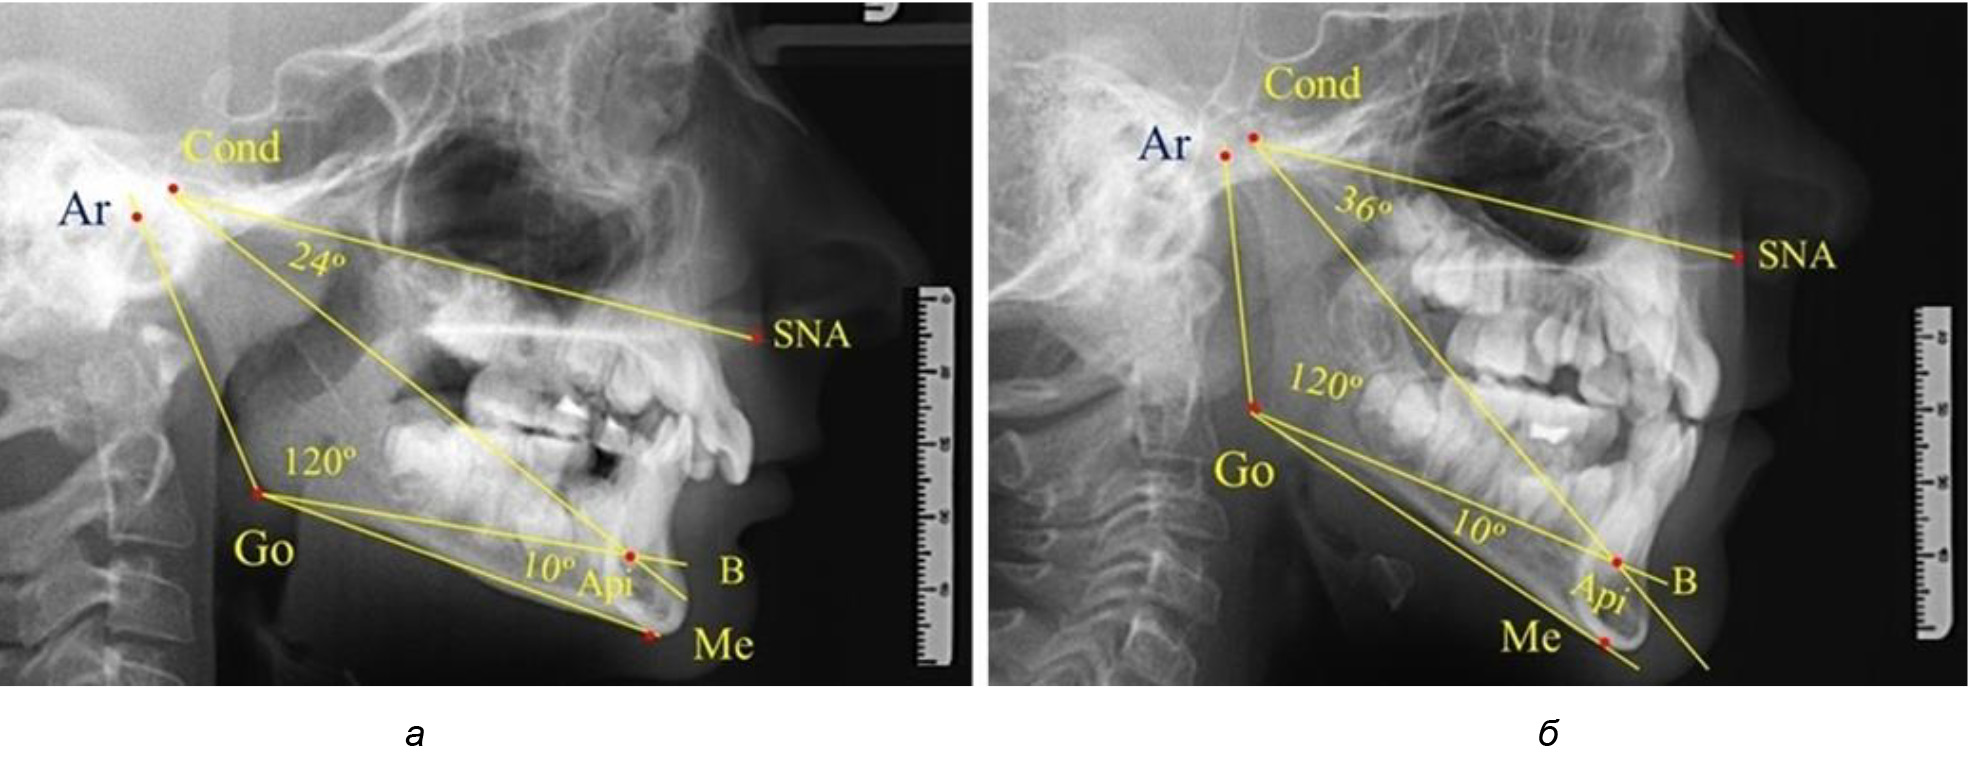

После смены всех молочных зубов (анализ 9 ТРГ) и после прорезывания вторых постоянных моляров (7 человек) происходил очередной этап подъема высоты прикуса с увеличением размеров костей гнатической части лица. Однако величина основного угла гнатической части лица SNA-Cond-Api, так же как в молочном и сменном прикусе, в норме составляла (30,02 ± 1,25)°, что не имело достоверных различий (р ˃ 0,05) с аналогичным параметром, анализируемом в других группах исследования. Угол нижней челюсти и его составляющие отличались вариабельностью параметров при различных показателях нижнечелюстного угла (рис. 6).

Рис. 6. Варианты 3D рентгенограмм детей после смены всех молочных зубов (а) и после прорезывания вторых моляров (б)

Таким образом, в периоде молочного прикуса с оптимальными окклюзионными соотношениями, несмотря на линейные размеры в вертикальном и сагиттальном направлении, которые, безусловно, меньше параметров взрослых людей, величина основного угла гнатической части лица SNA-Cond-Api соответствовала параметрам людей с полностью сформированным физиологическим прикусом постоянных зубов. Анализируя данные рентгенограмм детей в периоде сменного прикуса, отмечено, что величина основного угла гнатической части лица SNA-Cond-Api, так же как в молочном и постоянном прикусе, в норме составляла от 28 до 32°. В то же время угол нижней челюсти и его составляющие отличались вариабельностью параметров при различных показателях нижнечелюстного угла. Достоверных различий угла гнатической части после смены нижних медиальных резцов и прорезывания первых постоянных моляров (4 ребенка) не было; происходил очередной этап подъема высоты прикуса и увеличение линейных размеров костей гнатической части, однако угловые параметры были относительно стабильны. После смены всех резцов и замены первых молочных моляров первыми премолярами (6 человек) увеличивались линейные размеры при сохранившихся угловых показателях гнатической части лица (рис. 5).